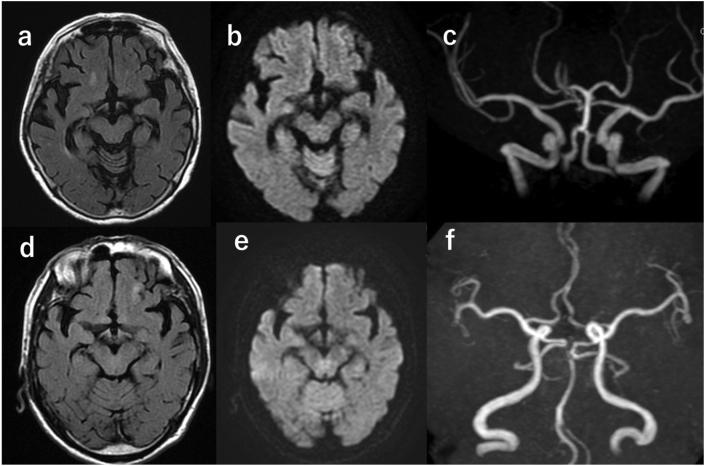

Cranial nerve III palsy, also known as oculomotor nerve palsy, may result from various causes; however, the etiology remains unknown in some instances. The aim of this case report is to present the authors' experience with two cases of idiopathic cranial nerve III palsy, together with a review of the literature. Case 1 is a 78-year-old woman and case 2 is a 75-year-old man, both having no history of trauma and no vascular risk factors. They presented to the authors' hospital with diplopia and palpebral ptosis and were diagnosed with idiopathic unilateral cranial nerve III palsy. They received oral steroids for treatment. One patient recovered completely within 3 months, while the other patient did not recover regardless of long-term follow-up. Idiopathic cranial nerve III palsy can occur in otherwise healthy individuals and often recover in several months. Careful examinations to rule out other causes and then steroid treatment should be considered after early diagnosis.

动眼神经麻痹,也称为第三脑神经麻痹,可能由多种原因引起;然而,在某些情况下病因仍不明。本病例报告的目的是介绍作者对两例特发性动眼神经麻痹的经验,并对文献进行综述。病例1是一名78岁女性,病例2是一名75岁男性,两人均无外伤史和血管危险因素。他们因复视和眼睑下垂到作者所在医院就诊,被诊断为特发性单侧动眼神经麻痹。他们接受了口服类固醇治疗。一名患者在3个月内完全康复,而另一名患者无论长期随访均未康复。特发性动眼神经麻痹可发生在其他方面健康的个体中,通常在几个月内恢复。应进行仔细检查以排除其他原因,早期诊断后应考虑类固醇治疗。